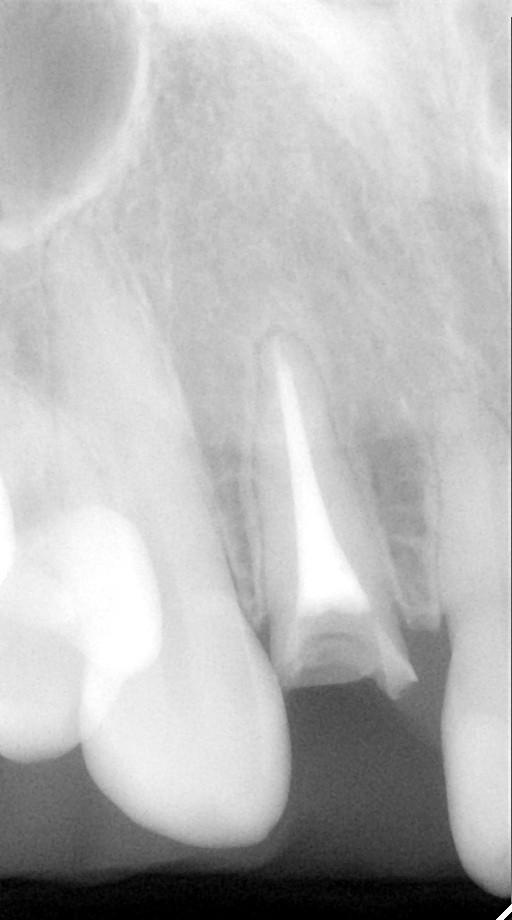

インプラント治療の症例紹介⑨

Before

After

抜歯後骨造成手術を行い、その後インプラント埋入手術を行いました。

外傷により歯根破折を生じたケース。骨欠損が大きかったので骨造成術を行い、審美ゾーンにインプラント補綴を行った症例です。